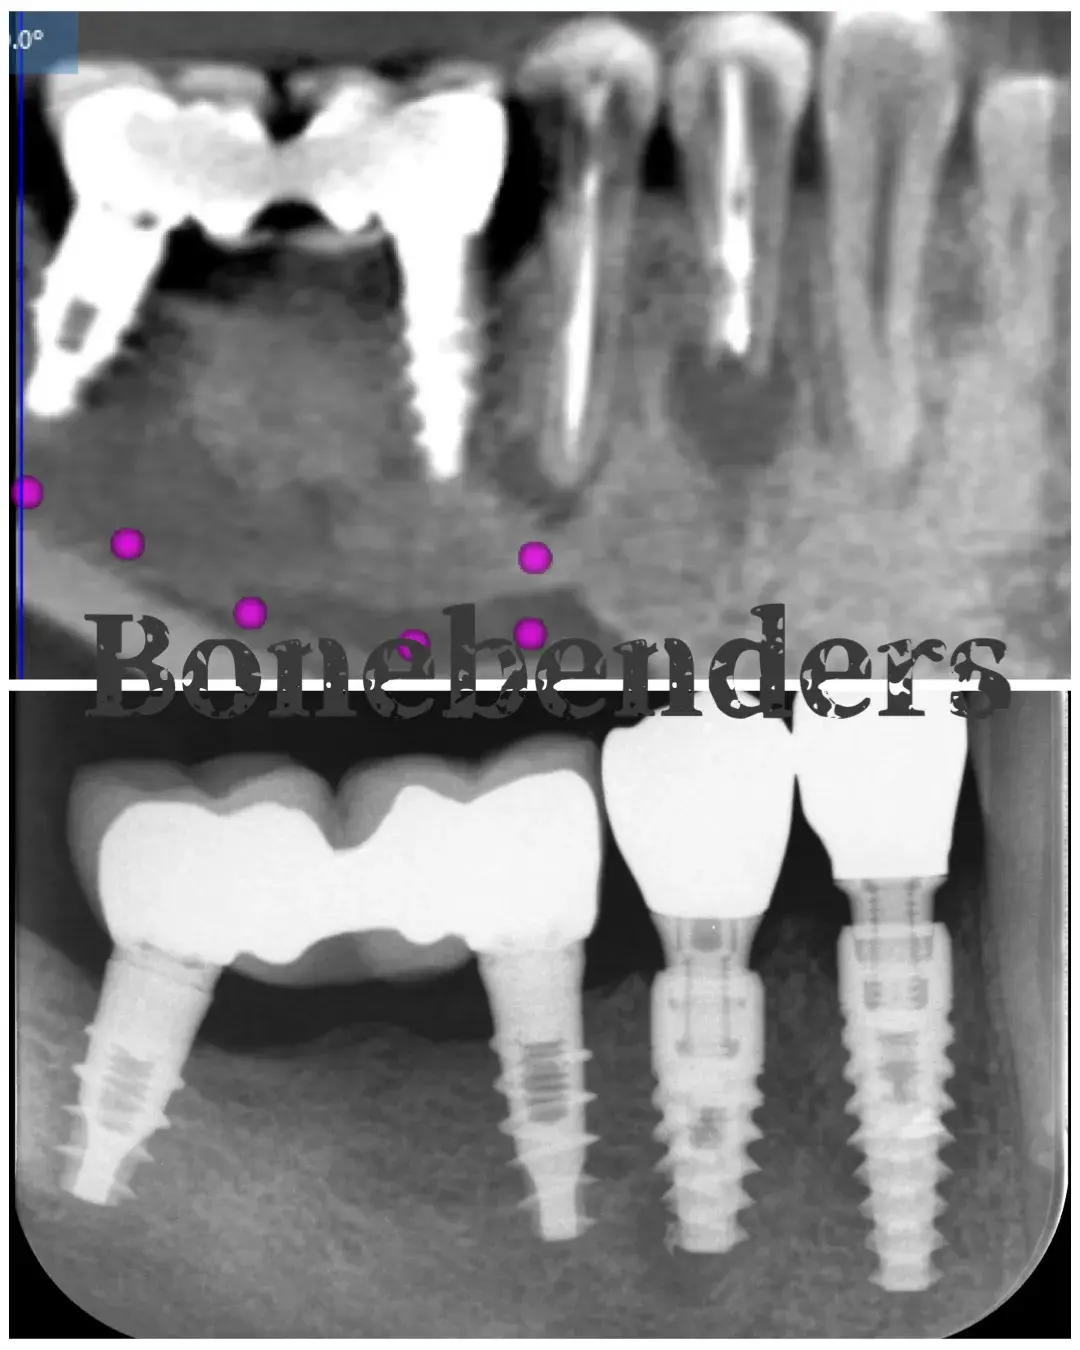

Caso clinico di sinus lift crestale immediato post-estrattivo con innesto eterologo e colla di fibrina, espansori Kalodon. Follow-up CBCT a 2 mesi.

Caso clinico di carico immediato su rialzo crestale del seno mascellare con espansori. Espansione apicale, stabilità >50 Ncm, provvisorio immediato e co...